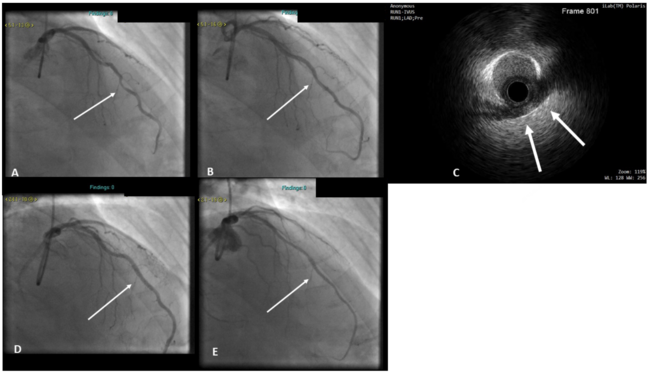

Patient 2. A 57-year-old male patient presented with frequent anginal pain on a background of aggressive primary prevention and antianginal medications. Coronary angiogram demonstrated a non-dominant right coronary artery (RCA), normal left main, normal left circumflex (LCX) artery and mid-LAD MB (Figure 2). Physiological assessment of the LAD revealed instantaneous wave-free ratio (iFR) of 0.88 and FFR of 0.80. IVUS revealed mild calcific atheroma in the tunneled segment. Due to refractory angina, the mid-LAD MB was stented with a 3.0- x 28-mm DES and postdilated with a 3.5-mm non-compliant (NC) balloon with optimal angiographic and IVUS results (Figure 2). Poststent FFR was 0.96. The patient had complete resolution of his symptoms with no angina and good exercise tolerance at recent 12-month follow-up. A repeat coronary angiography 32 months later showed no evidence of in-stent restenosis (Figure 2).

Patient 3. A 50-year-old patient presented with typical exertional angina. Coronary angiography demonstrated a mid-LAD MB. He was initially treated conservatively, but his symptoms persisted despite maximally tolerated antianginal therapy and he was readmitted for invasive ischemia testing and consideration for PCI. Physiological functional testing revealed an RFR value of 0.74 and FFR of 0.70. The LAD MB segment was therefore stented with a 3.0- x 28-mm DES and postdilated with a 3.5-mm NC balloon with optimal angiographic and IVUS result (Figure 3). The RFR value rose to 0.92 and the FFR to 0.93 post PCI. At 12-month follow-up, the patient has had no recurrent symptoms and is angina free. At 18 months post procedure, he developed atypical chest pain. Subsequent coronary angiography showed a widely patent stent in the LAD with no restenosis (Figure 3). His symptoms have subsequently resolved.